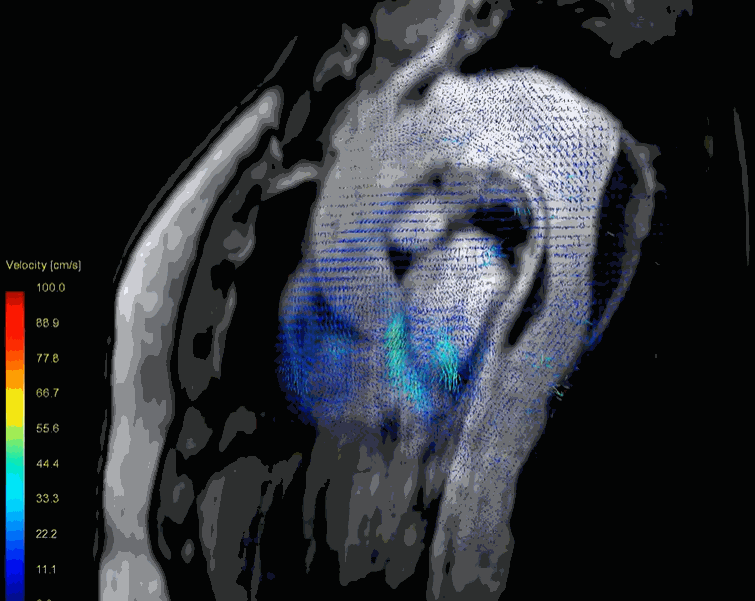

A rapidly focussed TTE usually confirms the diagnosis.TEE might be used but carries a small risk of directly aggravating dissection when performed in an unstable patient. Conventional CT provides good (but limited) information, spiral MDCT delineates the vascular anatomy in a more clear way. MRI probably scores over and adds flow dynamics.

(4D Phase-contrast MRI showing slow helical flow in the false lumen and high-velocity flow in the true lumen. Computational flow dynamics will help assess entry point, plane of dissection, calculate false lumen Index, pressure and wall stress in true lumen and Aortic branch compromise etc . Image courtesy. The Lancet Volume 385, Issue 9970, 28 February–6 March 2015, Pages 800-811)